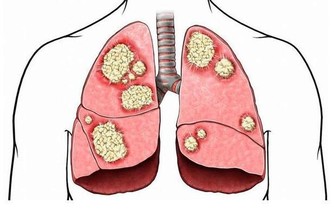

根據衛福部公布的民國103年十大死因,癌症連續33年蟬聯榜首,

占約所有死亡人數3成,平均每11分24秒就有一人死於癌症。

其實癌症發生的主要原因在於我們把食物吃下肚後無法排出體外的殘留物質,

這些老廢物質一旦堆積久了酸化後產生活性氧物質,便引發各種疾病。

卻有抗酸化、抑制癌細胞增殖、致癌物質無毒化、強化免疫力等功效,

免於身體受到體內毒素的侵害,除了能防癌外,

便秘、肥胖、高血壓、糖尿病、脂肪肝、肝炎、痛風、更年期障礙等症狀也有所改善。